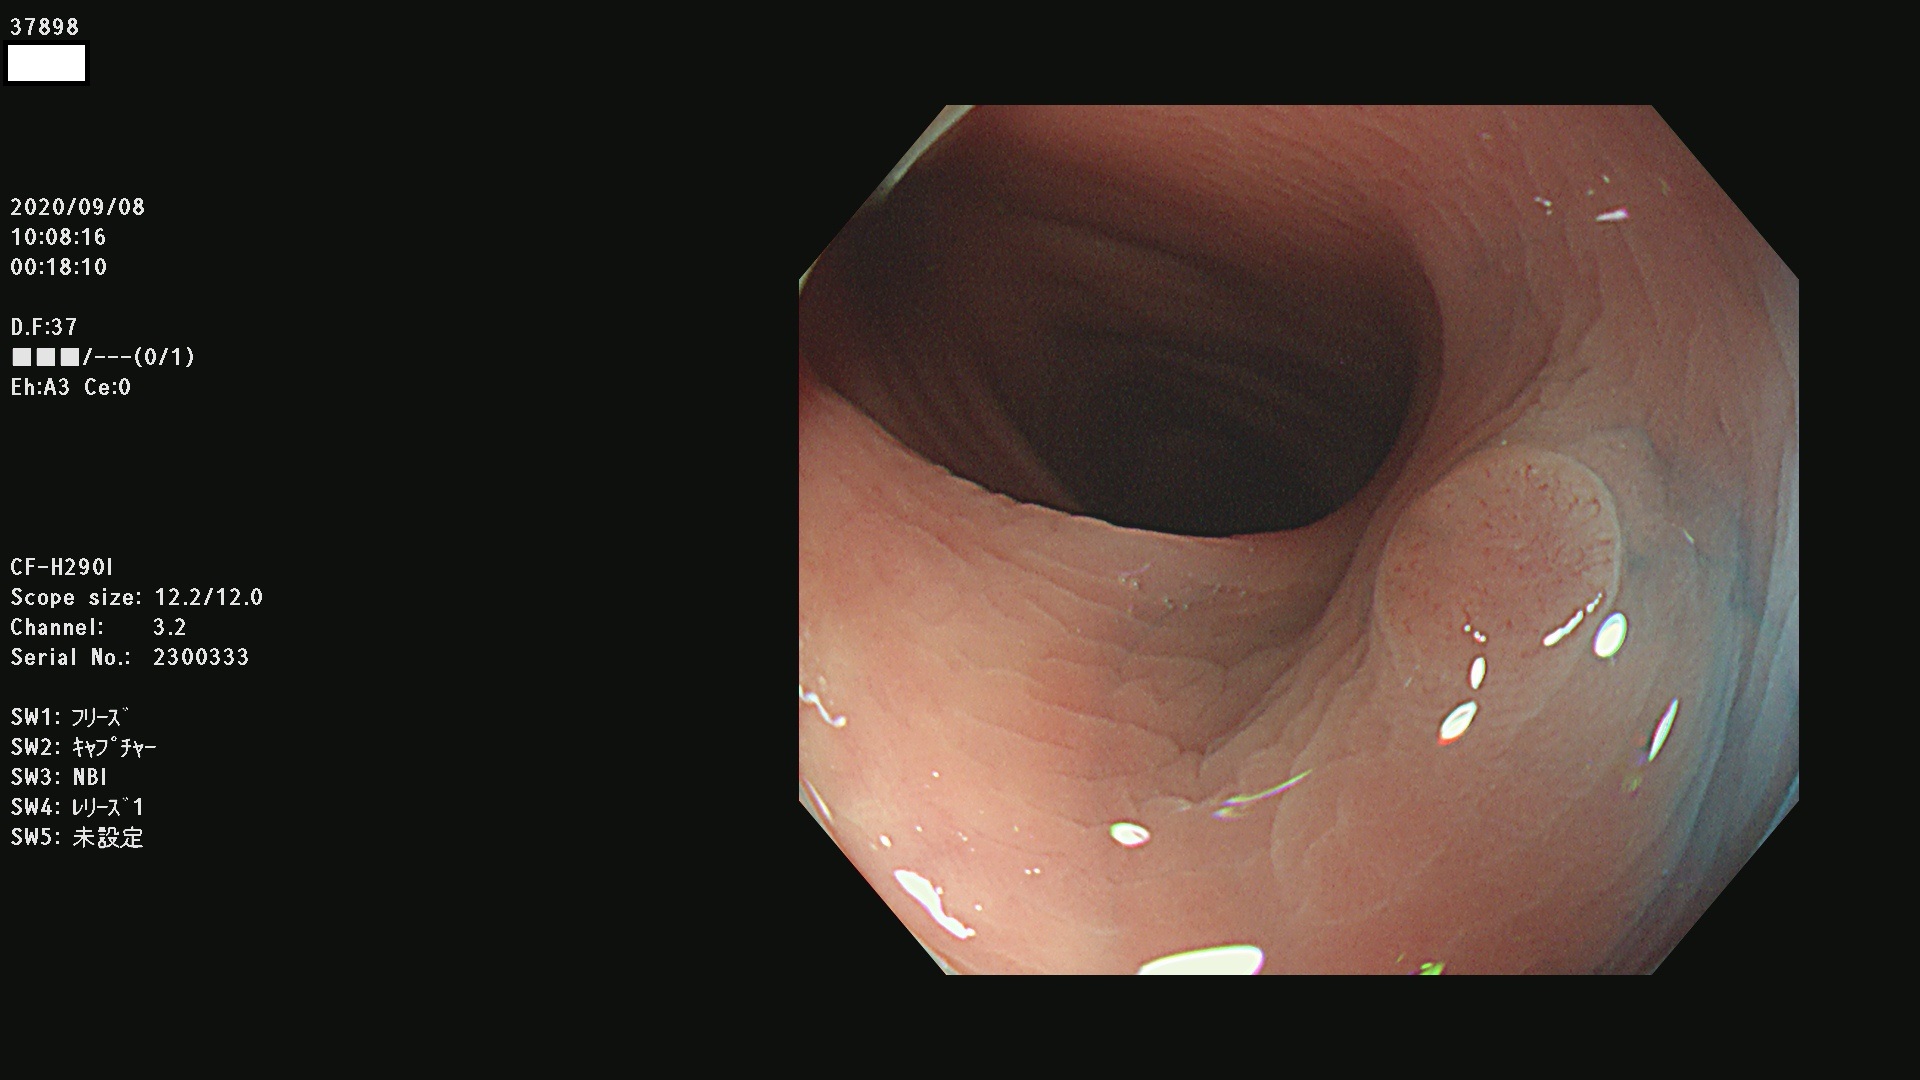

腺腫発見率 75 % (カルテ番号 37800〜37899の100名の方の検査結果で集計)大腸癌検診最新情報

以下のカルテ番号の方に腺腫(Adenoma,Group3〜5)が見つかりました(集計法)

37800(SSAPのみ) 37801 37802 37803 37804 37805 37806 37807 37808 37809(SSAPのみ) 37810 37811 37812 37813 37814 37815 37817 37818 37819 37820 37821 37822 37824 37825 37826 37827 37828 37829 37832 37833 37836 37837(SSAPのみ) 37839 37840 37842 37844 37845(SSAPのみ) 37847 37849 37850 37851 37852 37853(SSAPのみ) 37855 37856 37857 37860 37861 37862 37863 37864 37867 37868 37871 37874 37876 37877 37879 37880 37881 37882 37883 37886 37887 37888 37889 37890 37891 37892 37893 37894 37896 37897 37898 37899

発見困難で危険性の高い平坦型病変(上記100名より抽出) ![]()